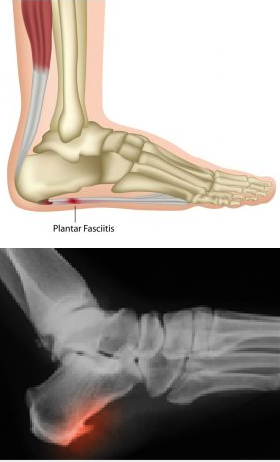

A fáscia plantar é uma faixa de tecido fibroso responsável por manter a arcada do pé. Estende-se do calcanhar até a base dos dedos, e funcionalmente forma uma estrutura contínua com o tendão de aquiles e os músculos da parte de trás da perna (gastrocnêmio e solear).

A fasceíte plantar ocorre quando a esta fáscia é excessivamente esticada ou tensionada, resultando em pequenas roturas no tecido, que por sua vez leva a uma inflamação continuada que é dolorosa. A inflamação continuada, por sua vez, leva ao depósito de cálcio nesta localização, visível na radiografia como um esporão no calcanhar.

Ao exame objetivo podemos suspeitar do diagnóstico pela reprodução da sintomatologia com a palpação dolorosa a nível da inserção da fáscia plantar e com manobras que provoquem o seu estiramento. O exame físico deve ser completo para que possam ser identificados fatores de risco que propiciem o aparecimento desta patologia (pé plano, pé cavo, contratura da cadeia posterior, …).

Geralmente o estudo é complementado com exames auxiliares de diagnóstico, como a ecografia e/ou a ressonância magnética. Consoante as alterações ao exame objetivo, poderá ser necessário o estudo complementar com radiografias em carga e ou TAC.